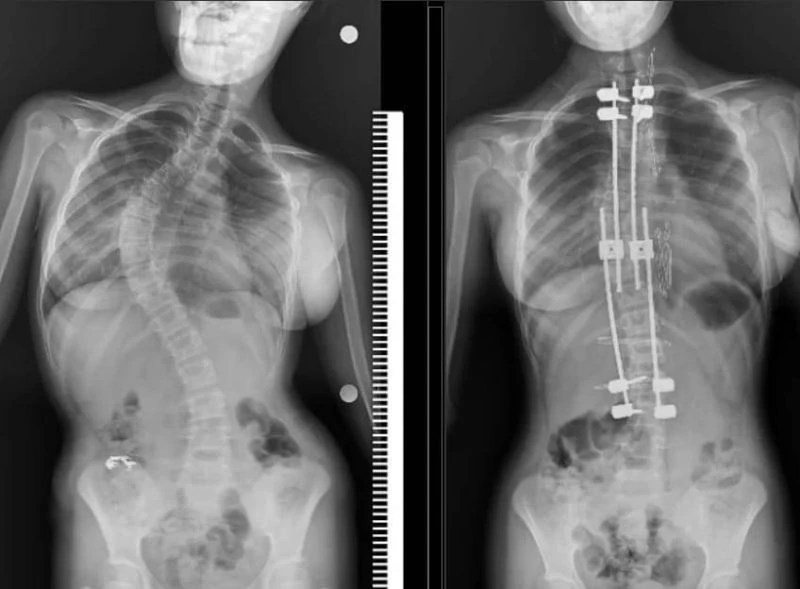

Samsun Eğitim ve Araştırma Hastanesi’nde ilk defa 10 yaşındaki bir çocuğa skolyoz (omurga eğriliği) ameliyatı yapıldı. Özel hastanelerde 300-500 bin TL arasında yapılan bu ameliyat kamu hastanesinde ücret alınmadan başarılı bir şekilde gerçekleştirildi.

Samsun’un Bafra ilçesinde yaşayan 10 yaşındaki Zümra Demircioğlu bel ve sırt bölgesinde aşırı ağrı ve günlük aktivitelerini yapmakta zorlanma şikayetleri nedenleriyle Samsun Eğitim ve Araştırma Hastanesi’ne başvurdu. Burada çekilen röntgen ve yapılan tetkikler sonucunda 75 derece omurga eğriliği tespit edilen minik Zümra için ameliyat kararı verildi. Büyüme koruyucu sisteminin uygulandığı ameliyatta minik Zümra’nın omurgası düzeltildi. Özel hastanelerde ortalama 300 ile 500 bin TL arasında yapıldığı öğrenilen bu ameliyat artık Samsun Eğitim ve Araştırma Hastanesi’nde ücretsiz olarak gerçekleştiriliyor.

Ameliyat hakkında bilgi veren Dr. Ömer Bozduman, "Bu gibi durumlarda uzayan rot dediğimiz bir sistem uyguluyoruz. Bunun nedeni çocukları yaşı küçük olduğu için füzyon dediğimiz kaynatma ameliyatı yaparsak akciğerlerinde yetersiz gelişme, göğüs kafeslerinde yetersiz gelişme ve kanallarında yetersiz gelişme oluşabileceği için büyüme koruyucu cerrahi yapıyoruz. Büyüme koruyucu cerrahinin diğer füzyon cerrahisinden alternatifi şudur: Düzenli aralıklarla düzeltme yapıyoruz. Çocuk büyüdükçe biz de bu sistem anestezi altında ya da anestezisiz olarak uzatarak çocuğun yeterli omurga büyüklüğüne ulaştıktan sonra yeterli kalıcı ameliyatı gerçekleştiriyoruz. Anestezi hocamız Doç. Dr. Serkan Turgal yardımı ile bu ameliyatı başarıyla gerçekleştirdik. 10 yaşındaki hastamıza büyüme koruyucu sistemi yerleştirdik. Düzenli aralıklarla uzatmalarını yapacağız. Nihai ameliyatını omurgası büyüdükten sonra gerçekleştireceğiz. Eğitim ve Araştırma Hastanesi olarak bir ilki gerçekleştirdik. Hastamız gayet iyidir. Birinci günün kalkıp yürüdü. Dördün gün sonra taburcu ettik. Herhangi bir nörolojik veya başka bir sorunla karşılaşmadık. İhtiyacı olan tüm hastalarımıza Samsun Eğitim ve Araştırma Hastanesi olarak devletimizin imkanlarıyla bu hizmeti ücretsiz olarak veriyoruz. Aileler bu semptomlar hakkında dikkatli olmalıdır. En ufak şüphede polikliniklerimize bekliyoruz. Bizler yardımcı olacağız" diye konuştu.